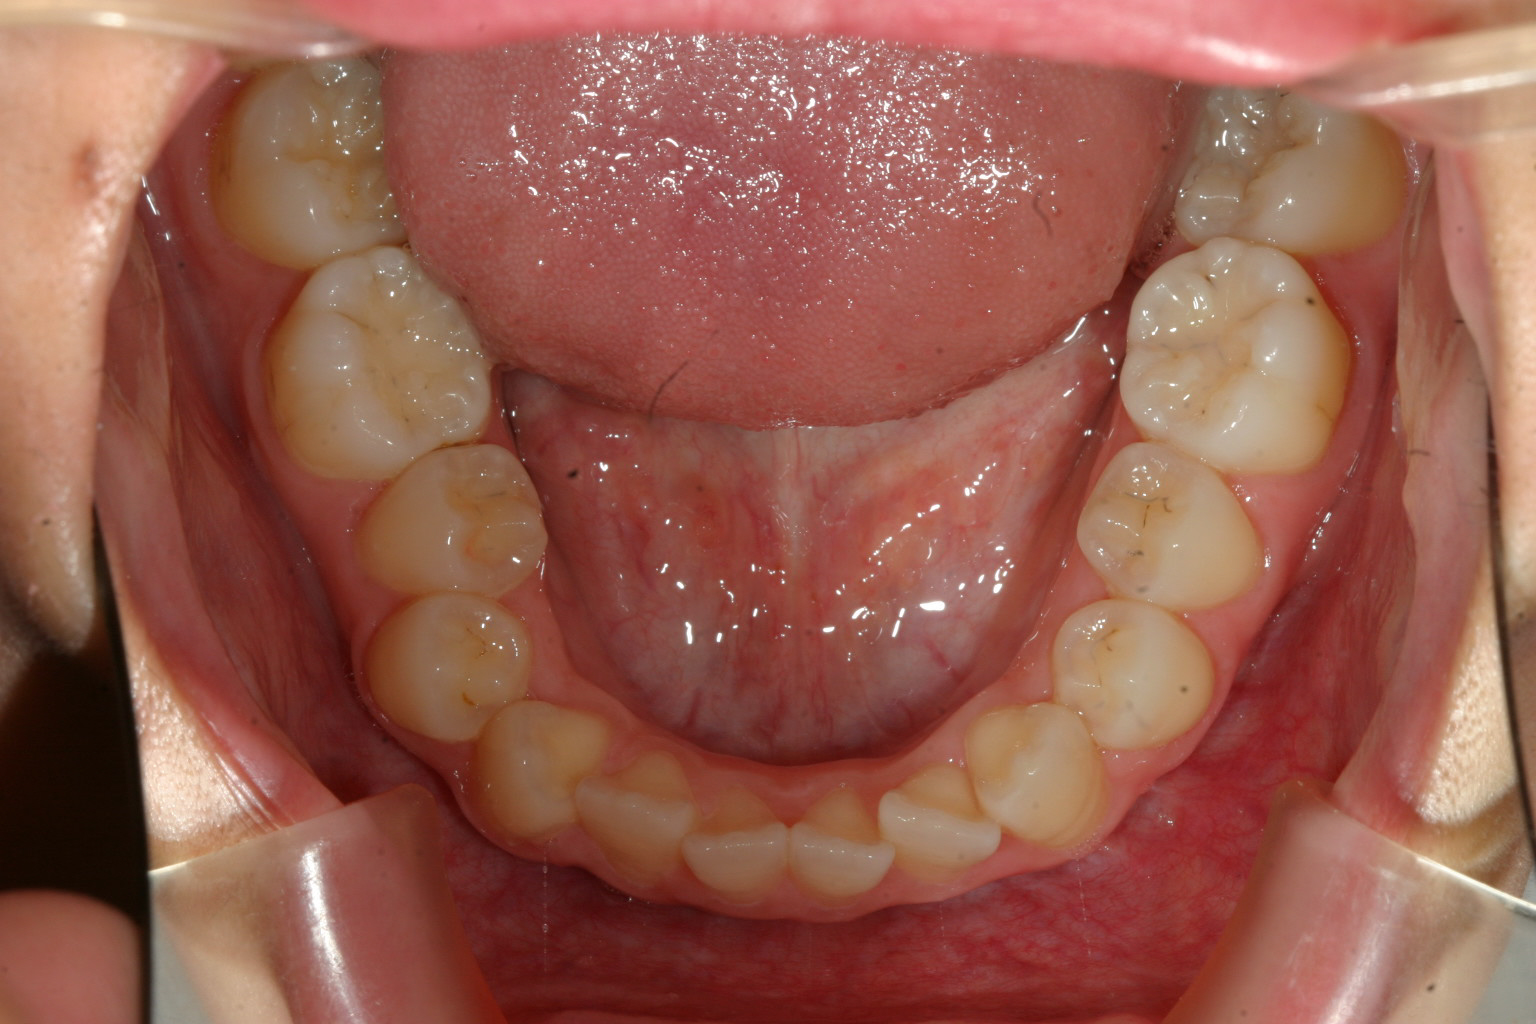

アーチが狭い為に前歯が並びきらずガタガタしてます。

下顎の少し叢生が有ります。

少し受け口ですね!